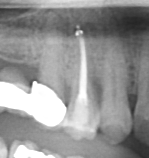

Any site is a potential candidate as long as there is adequate bone both surrounding, as well as past the tooth root(s), to allow for an ideal restorative position with good initial stability.